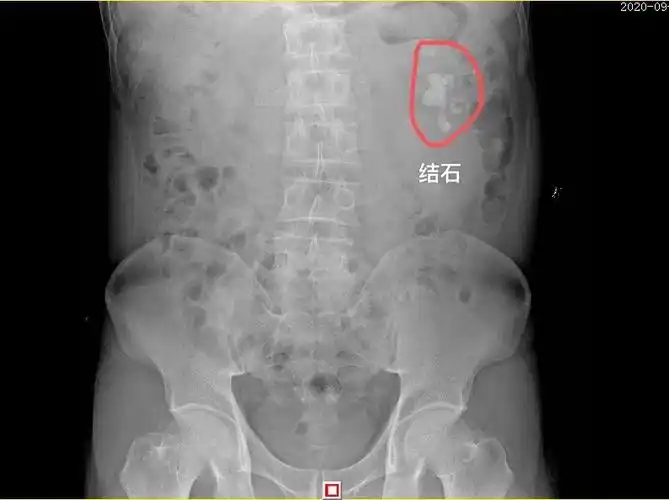

肾里长出肾结石,当心会毁肾,1杯偏方茶,排石又止痛

肾结石